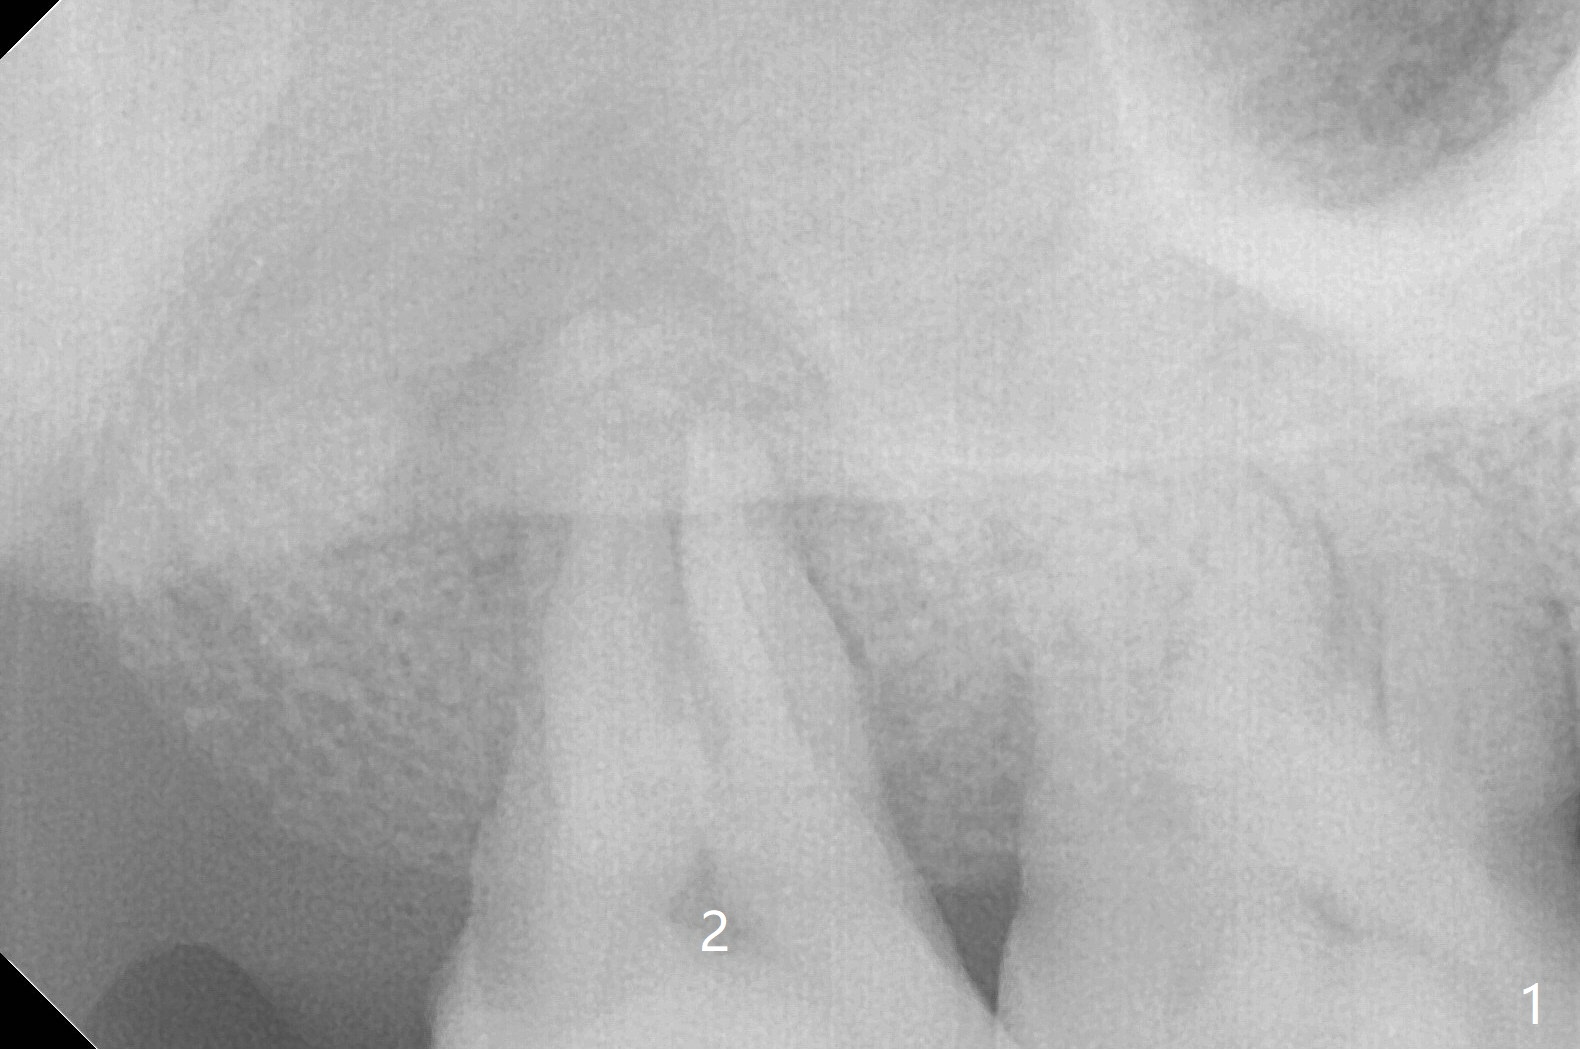

A 55-year-old woman requests extraction of the tooth #2 with pain and mobility a few weeks post SRP (Fig.1) and finally agrees with socket preservation (Fig.2,3 *). In fact the mesiobuccal root appears to have been fractured. She is a heavy bruxer (nuts). There is a large amount of granulation tissue in a large single socket. After suture fixation over Osteogen plug and allograft (*), a prefabricated band (B) and loop (L) are cemented in place. Periodontal dressing is applied mainly underneath the loop for wound protection and bone graft and membrane fixation. The central portion of the periodontal dressing remains in place over the socket opening 1 week postop (Fig.4). The removable distal portion of the loop dislodged 23 days postop. The free end of the fixed mesial portion of the loop is irritating; the patient returns the following day. After removal of the spacer, the socket appears to have healed (Fig.5). No bone graft has been lost (Fig.6 *, as compared to immediately postop (Fig.2,3)). Return to Upper Molar Immediate Implant, Trajectory Xin Wei, DDS, PhD, MS 1st edition 04/13/2019, last revision 01/06/2020